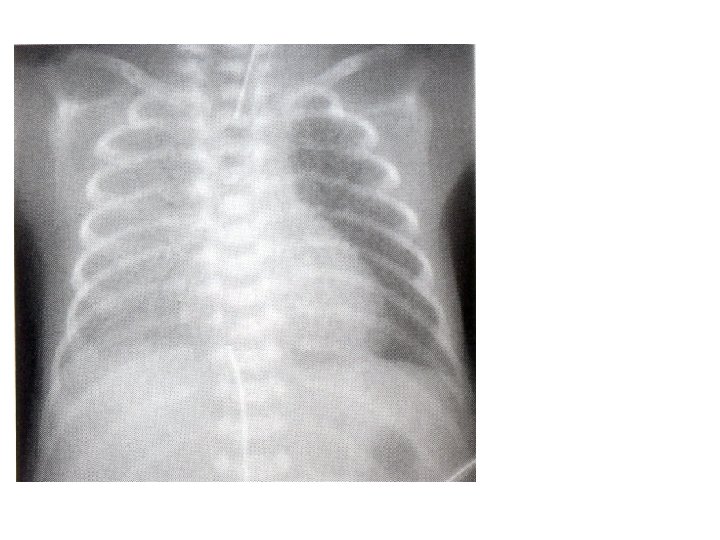

24 с. ж. Гиперинфляция, деформация сосудистого рисунка, летнообразные уплотнения, мелкоочаговые просветления – начинающийся фиброз (БЛД III-IV стадия)